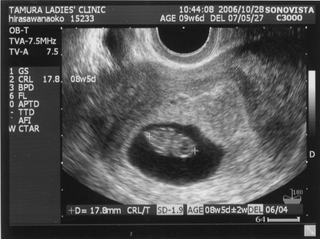

5ヶ月(18週と5日) 体重:262g BPD(頭を上から見た耳から耳の幅のような感じ):46.8㎜ FTA(お腹の断面):15.9平方㎝ FL(大腿骨長 太ももの骨の長さ):22.7㎜ 6ヶ月(22週と5日) 体重:602g BPD(児頭大横径 頭を上から見た耳から耳の幅のような感じ):57.6㎜ FTA(体幹横断面 お腹の断面):26.6平方㎝ FL(大腿骨長 太ももの骨の長さ):38.1㎜ まだこの頃は顔と上半身が収まっていました。 検診は妊娠23週までは、4週に一度なのでドキドキとワクワクです。 ちゃんと成長してるかなあなんて考えて行って、 心音をきいたり、エコーを見て毎回安心と喜びがわいてきます(*^_^*) たった4週で、体重は3倍近くにも!かわいいなあ☆ 6ヶ月の検診日ダンナっちは仕事だったから、 エコー写真を携帯で撮って送ると、 『目ん玉でてない!?』 と返事が返ってきました。 眼球がそう見えるんだろうけど、目のとても細いダンナっちには 衝撃的だったんですね(^。^;) 胎動を初めて感じた日をわたしはわかりません・・・ メモにとるなり、日記にかくなりすることをすっかり忘れてしまって、 今となって後悔<<o(>_<)o>> ダメな母親めっ と思いつつも、わたしらしいと感じ笑っています(^_^;) 12月の末に友達に、 「腸の動きか!?って思うのはあるんだけどまだよくわかんない」 と言ったのを覚えているので、12月の終わりから1月にかけての あたりなんでしょうね。 いつの間にかポッコポッコしていました! ベイビーこんなママだけどよろしく└|∵|┐♪┌|∵|┘ 6ヶ月までは、普通にそれまで履いていたジーンズも入っていたんだけど、 6ヶ月終わるころには、急に入らなくなってビックリしました~ 食生活の変化も特になかったです。 あ、ポテトチップスあまり自分で 買わなかったのに、1週間くらいブームの時期がありました!妊娠による影響かな!? 今、ベイビーはしゃっくりをしているみたいです |